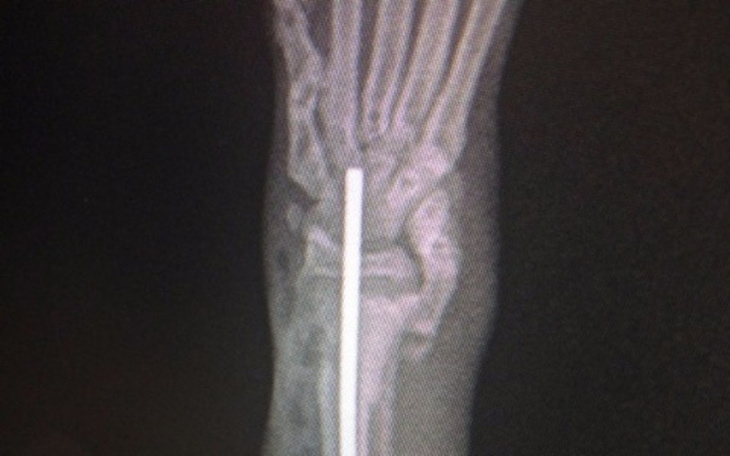

Złamanie przynasadowe kości przedramienia promieniowej, zwichnięcia kości lokciowej w stawie nadgarstkowym konczyna przednia prawa.

Stabilizacja zlamania za pomocą gwoździa srodszpikowego